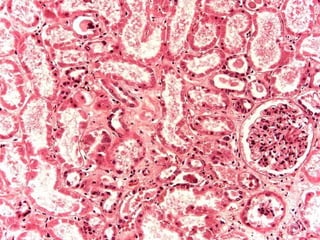

B - Necrosi Tubulare Acuta Tossica Sostanze ENDOGENE in eccesso • Emoglobina libera emolisi • Mioglobina traumi tetano • Bilirubina epatite acuta ittero ostruttivo

Necrosi tubulare acuta da mioglobina